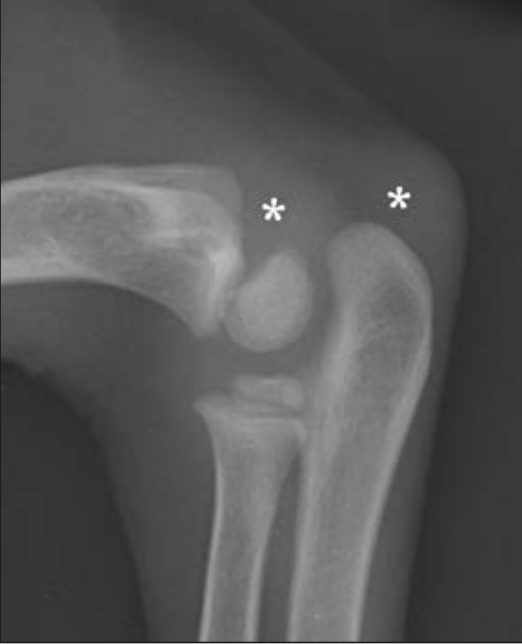

If this is an 8 week old Rottweiler, what are the * indicating?

Future ossification centres of the olecranon (ulna) and medial epicondyle (humerus).